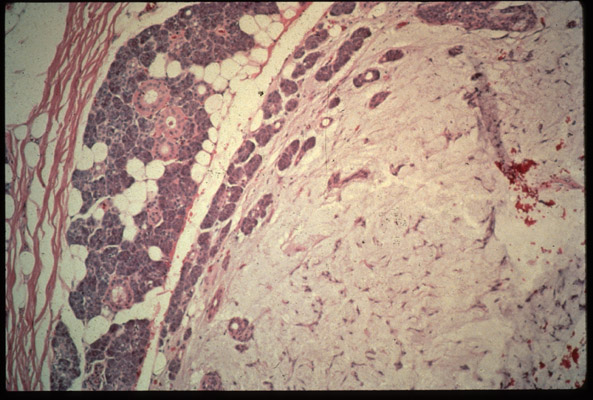

Histologic findings

cellular microscopic image